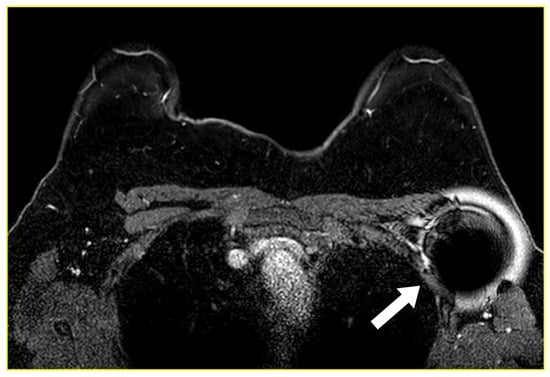

2.4. Magnetic Seed